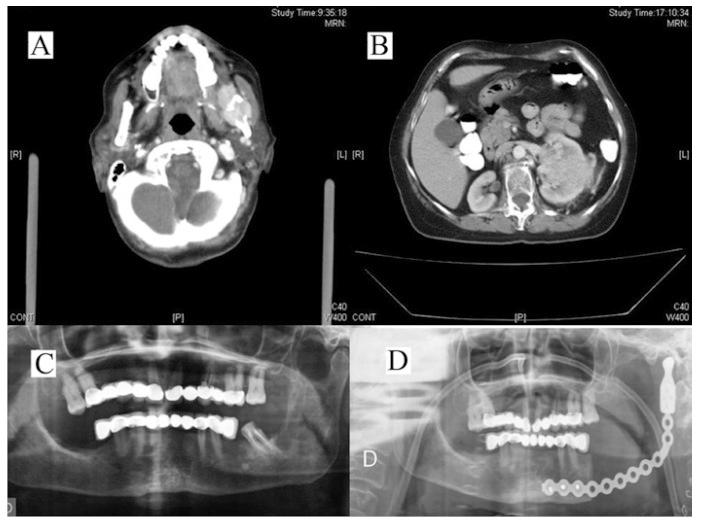

We present three cases of maxillofacial metastasis of genitourinary tumours, two clear cell renal adenocarcinoma and squamous cell carcinoma of the uterine cervix. The patients were referred our hospital service for diagnosis and treatment, after having been initially evaluated for buccodental symptoms.

我们报告了三例泌尿生殖系统肿瘤颌面转移的病例,两例为肾透明细胞腺癌,一例为宫颈鳞状细胞癌。这些患者最初因口腔牙齿症状就诊于我们医院,随后被转诊至我们的服务部门进行诊断和治疗。